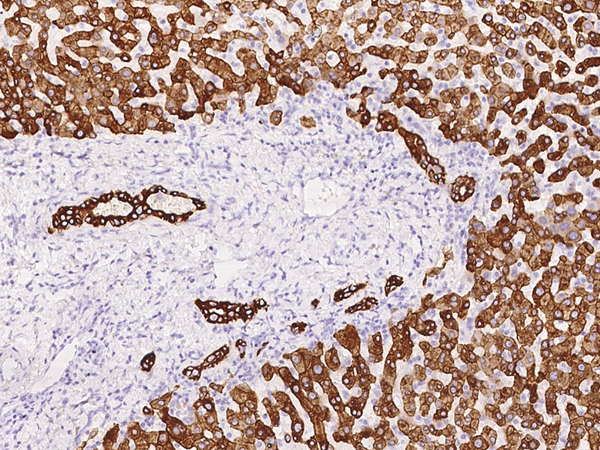

IHC (Immunohistochemistry)

(Immunochemical staining of human Cytokeratin 8 in human liver with mouse monoclonal antibody at 1:2000 dilution, formalin-fixed paraffin embedded sections.)